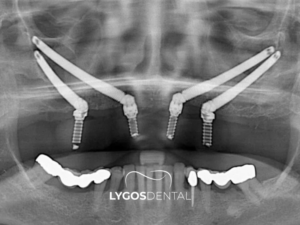

Zigoma implant standart implantlardan çok daha uzun yapıya sahip özel titanyum vidalardır. Bu vidalar üst çenede kemik erimesi olan hastalarda elmacık kemiğine sabitlenir. Elmacık kemiği tıp dilinde zigomatik kemik olarak adlandırılır ve oldukça serttir. Cerrahi işlem klinik ortamında uzmanlar tarafından lokal anestezi veya sedasyon altında yapılır. Açılı bir şekilde yerleştirilen vidalar üst çenedeki protezleri taşımak için güçlü bir temel oluşturur. Çene kemiğinin yetersiz olduğu bölgeler atlanarak doğrudan sağlam anatomik noktalara ulaşılır. İşlem sonrasında genellikle aynı gün içinde sabit geçici protezler vidaların üzerine yerleştirilir. Hastalar aylarca dişsiz kalmadan günlük sosyal yaşantılarına oldukça konforlu bir şekilde dönebilir. Fonksiyonel kayıpların hızlıca giderilmesi psikolojik açıdan hastalara büyük bir moral kaynağı olur.

Standart implantlar genellikle sekiz ile on milimetre uzunluğunda üretilen kısa titanyum vidalardır. Bu kısa vidaların tutunabilmesi için üst çenede yeterli kemik kalınlığı bulunması şarttır. Zigoma implantlar ise otuz ile elli milimetre arasında değişen özel uzunluklara sahiptir. Geleneksel yöntemlerde kemik yetersizse aylar süren sinüs kaldırma ve greft işlemleri planlanır. Elmacık kemiği destekli sistemlerde ise bu uzun ve yorucu cerrahi aşamalar çoğunlukla atlanır. Özel vidalar sinüs boşluğunun yanından veya içinden geçerek doğrudan elmacık kemiğine sabitlenir. Bu sayede tedavi süresi büyük oranda kısalır ve hastanın klinik konforu artar. Standart yöntemlerde dişsiz bekleme süresi uzunken bu sistemde aynı gün protez takılabilir. Maliyet açısından değerlendirildiğinde ek cerrahi işlemleri azalttığı için hastalara avantaj sağlar.

Başarılı bir operasyon için tedavi öncesinde oldukça detaylı bir medikal analiz süreci yürütülür. Hastanın genel sağlık tablosu ve kan değerleri uzmanlar tarafından kapsamlıca incelemeye alınır. Hastanın çene anatomisini incelemek için üç boyutlu dijital tomografiler detaylıca çekilerek durum değerlendirmesi yapılır. Elmacık kemiğinin yoğunluğu ve sinüs boşluklarının konumu dijital ortamda milimetrik olarak özenle hesaplanır. Titanyum vidaların yerleştirileceği açılar sanal cerrahi yazılımlar üzerinden dikkatli bir şekilde planlanarak operasyona hazırlanılır. Ağız içinde iltihaplı veya çekilmesi gereken dişler varsa cerrahi öncesinde durumları dikkatlice değerlendirilir. Yapılacak protezlerin estetik tasarımı hastanın yüz hatlarına ve dudak yapısına göre özel olarak şekillendirilir. Bu medikal hazırlık aşamaları operasyon sırasında oluşabilecek riskleri en aza indirmeyi büyük oranda hedefler. Planlı ilerleyen bir cerrahi süreç hastanın klinik koltuğunda geçirdiği zamanı oldukça rahatlatır. Dijital teknolojilerin kullanımı alınacak sonuçların öngörülebilir olmasını büyük oranda destekleyerek estetik başarıyı artırır.

Zigoma implant cerrahisi hastanın kemik durumuna bağlı olarak genellikle iki ile dört saat arasında tamamlanır. İşlem sırasında ilgili çene bölgesi uyuşturularak titanyum vidalar dijital ortamda planlanan açılarla dikkatlice yerleştirilir. Cerrahi operasyonun ardından aynı gün içinde laboratuvar ortamında hazırlanan geçici sabit protezler vidalara güvenle takılır. Hastalar aylarca sürecek dişsizlik döneminden kurtularak sosyal yaşantılarına çok kısa sürede geri dönme imkanı bulur. Titanyum vidaların elmacık kemiği ile sağlıklı bir şekilde kaynaşması ortalama dört ile altı ay civarında sürer. Bu uzun iyileşme dönemi bittikten sonra kalıcı porselen protezlerin yapım aşamasına geçilerek tedavi süreci noktalanır. Zaman açısından hastalara büyük konfor sağlayan planlı bir estetik yaklaşımdır.